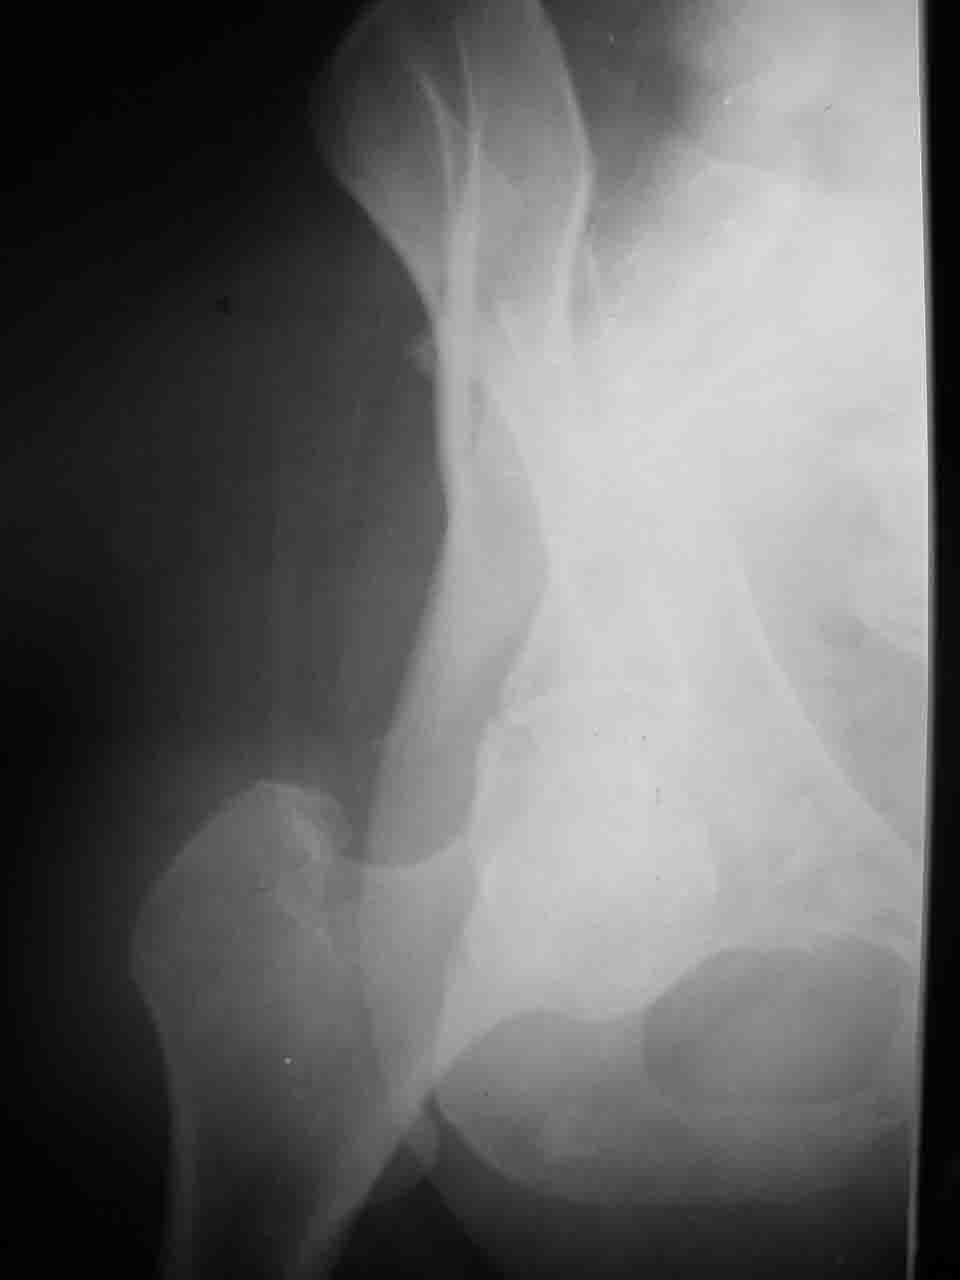

А какой отдел вертлужной впадины более важен передний или задний? Чем был обусловлен выбор доступа к суставу? Проще говоря, почему вы пошли передним доступом на двухколонный перелом? Мне понятны ваши сомнения, когда не удется сделать все что хотелось бы. В данном случае доступ должен быть чрезвертельным боковым (как и советовал Рунков) или двумя доступами.

Логика подсказывает, что все-таки лучше иметь анатомически полноценную впадину, хотя ранее упоминалось состояние вторичной конгруэнтности и одно наблюдение у меня есть, когда у больного с полностью нарушенной анатомией впадины и подвывихом головки бедра кзади и кверху боли отсутствовали при относительно достаточном для стиля жизни больного объёме движений. Но это только одно наблюдение и кроме перелома впадины у этогобольного была и тяжелая ЧМТ в анамнезе. Основываясь на формулировке структуры ацетабулюм Э. Летурнеля - как перевернутой буквы Y, впадина для полноценной функции сустава должна иметь сферичность, соответствующую размеру головки бедра и если один из компонентов в дефиците, то функциональные последствия рано или поздно проявятся.

> передним доступом на двухколонный перелом?

Илеофеморальный доступ не совсем передний и сравнительно с илеоингвинальным, и Кохера-Лангенбека открывает весь наружный таз кроме самых передних отделов лонных костей, фиксацию которых я не ставил в задачу. Обширность диссекции, большая длительность операции и более высокий риск гетерооссификации - отрицательные моменты в обмен на возможность легче ориентироваться.

Вопрос доступа к вертлужной впадине при остеосинтезе задача не простая. Конечно, у Летурнеля и Тайла всё давно описано, нам остается только брать на вооружение. Но сами понимаете, что не бывает двух одинаковых ситуаций, поэтому в каждом случае вопрос решается сугубо индивидуально. Наша главная цель - восстановить анатомию с нанесением минимальной дополнительной травмы тазобедреннному суставу, думаю с этим никто не поспорит. Расширенный илиофеморальный доступ уж слишком травматичен (как сказал один коллега "таз лежит отдельно, больной отдельно").Стоит ли делать из пациента анатомический препарат для того чтобы легче ориентироваться. Да и нужно ли собирать всю "мозаику"? Мы применяли при таких операциях своеобразную операционную хитрость - сначала устраняли грубое смещение крыла под гребнем с фиксацией так называемой "плавающей" пластиной (временно фиксированной на двух винтах)- доступ или продлевали боковой, или делали небольшой дополнительный разрез над гребнем. Это позволяло устранить грубое смещение и захождение отломков тела повздошной кости, что значительно облегчало репозицию и остеосинтез впадины над сводом. Основное внимание конечно же уделяли нагружаемому задне-верхнему отделу. Сообщите ваш адрес, пришлю схемы и рентгенограммы.